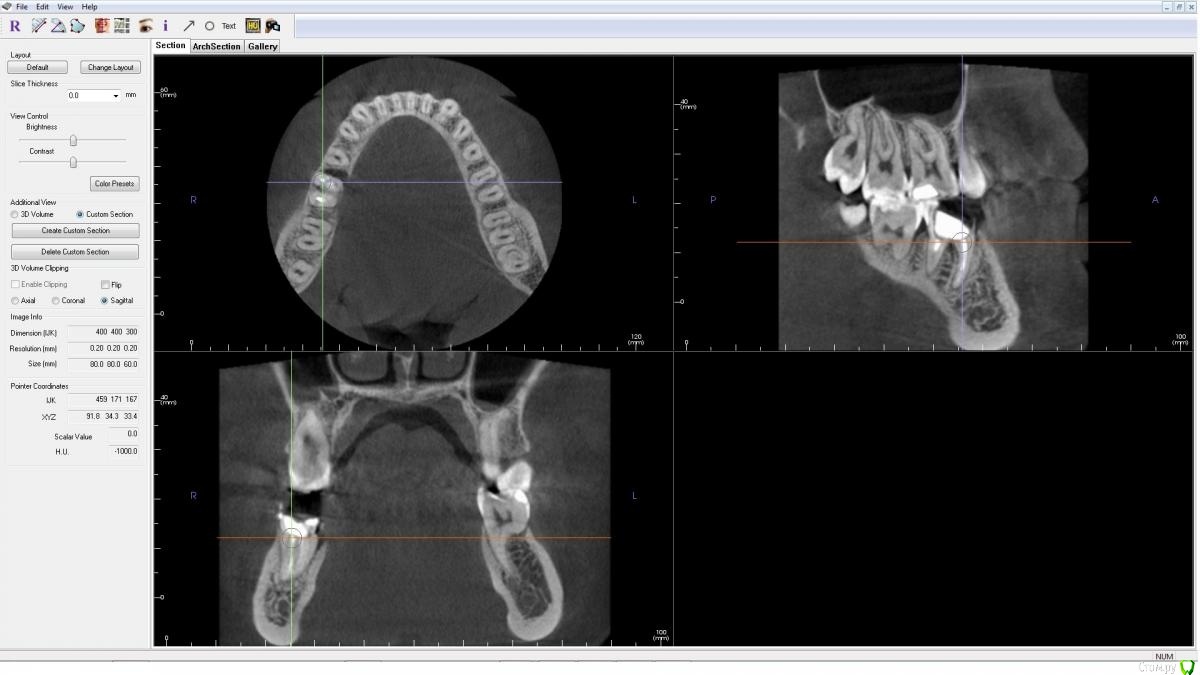

AlenaDM Опубликовано 17 февраля, 2021 Поделиться Опубликовано 17 февраля, 2021 (изменено) Добрый день.Сильно разрушен зуб. Ищу варианты протезирования. Уже посетила нескольких врачей, у всех вариант один - удаление и установка импланта, но возможно кто-то сможет помочь/подсказать другой вариант так сказать, можно ли обойтись "меньшей кровью".КТ из клиники прилагаю (открывается, к сожалению, только в Windows 8 и ниже, формат .exe)Спасибо!https://drive.google.com/file/d/1J0UHeSeCaEhpX65WpDZoImWtN_fYxXUO/view?usp=sharing Изменено 17 февраля, 2021 пользователем AlenaDM Ссылка на комментарий

wladdX Опубликовано 17 февраля, 2021 Поделиться Опубликовано 17 февраля, 2021 На мой взгляд показано удаление. Ссылка на комментарий